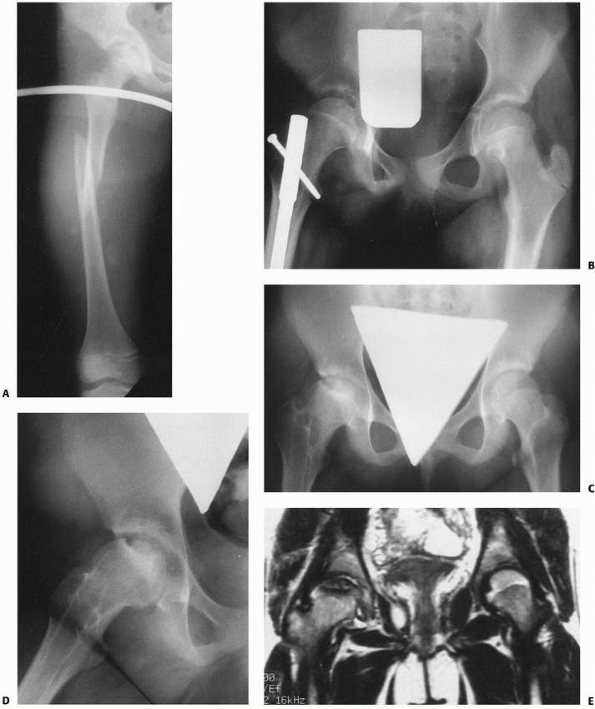

treated with intramedullary rodding, either as delayed or primary

and others in the early 1990s alerting surgeons that antegrade

intramedullary nailing. Recently, however, locked antegrade femoral

nailing for pediatric femoral fractures has enjoyed a resurgence of

interest with the introduction of newer generation implants that allow

a very lateral trochanteric entry point. These newer implant systems

Antegrade locked intramedullary fixation is particularly valuable for

femoral fractures in adolescents. Comparative studies by Reeves et al.170 and Kirby et al.,113

as well as retrospective reviews of traction and casting, suggest that

femoral fractures in adolescents are better treated with intramedullary

fixation11,30,47,68,69,73,90,108,113,123,197,210,212 than with traditional traction and casting (Table 22-3). Kanellopoulos et al.107